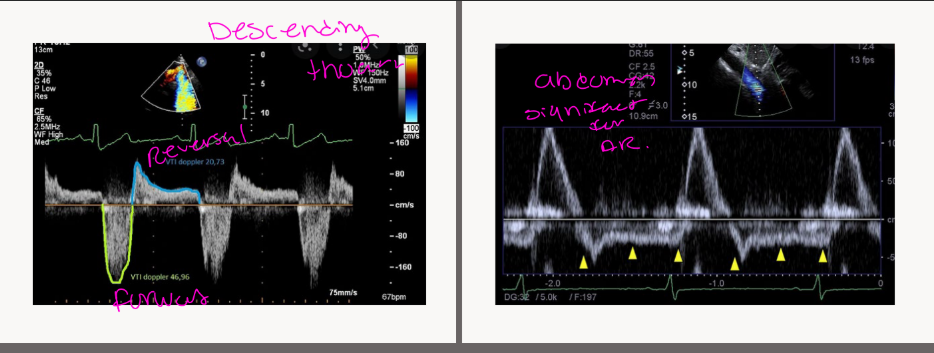

Shape of CW Doppler reflects?

Severe AR may become asymmetrical

reflecting

Shape of CW Doppler reflects pressure

changes

reflecting rapid equalization of pressure

ECHO FEATURES

Left atrium dilated *chronic

ā Increased diastolic filling pressures

Pulsatile aorta

- Flow reversal in aorta (descending

and abdominal)

Evidence of pulmonary hypertension

- Elevated TR velocity

- Dilated IVC/hepatic veins

PW DOPPLER

INTERROGATION

OF REVERSALS

REVERSALS IN THE AORTA